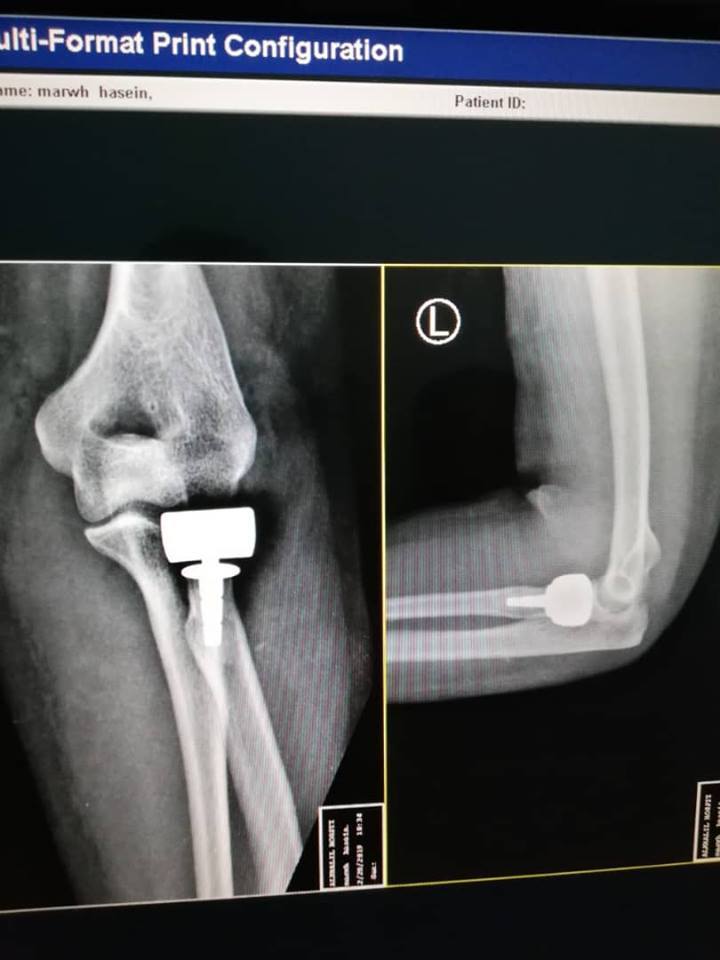

زراعة رأس صناعي لمريضة تعاني من كسر مركب في رأس عظمة الساعد

أجريت بمستشفى الخليل خلال الأيام الماضية عملية جراحية لمريضة تبلغ من العمر”35″، تعاني من كسر مركب في رأس عظمة الساعد .

العملية التي أجراها الدكتور” حسين الرجباني”،استشاري جراحة العظام والمفاصل كللت بالنجاح التام بتغير رأس عظمة الساعد برأس صناعي، وأكد الدكتور” الرجباني”، عقب العملية التي استمرت ساعة واحدة بأن هذه العملية من العمليات المعقدة، ولأول مرة تجري في ليبيا.

وأشاد بالجهود التي بذلها الفريق الطبي المرافق له لضمان نجاح العملية، موضحاَ بان حالة المريضة في تحسن ملحوظ وسوف تعافى خلال الأيام القادمة بشكل نهائي وتعود لممارسة حياتها بشكل طبيعي.